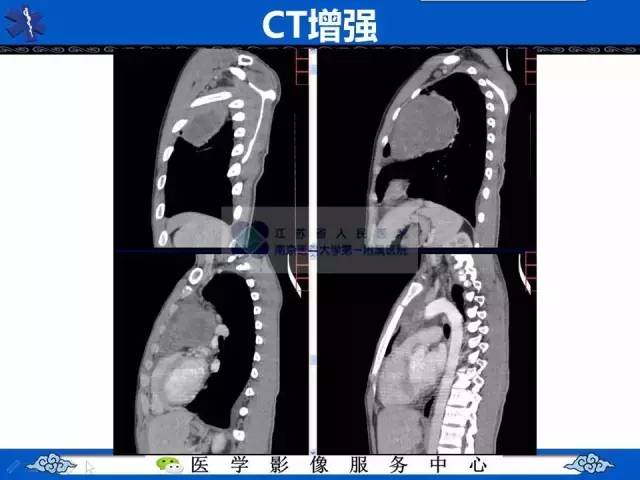

【病例】纵隔内胚窦瘤1例CT影像表现